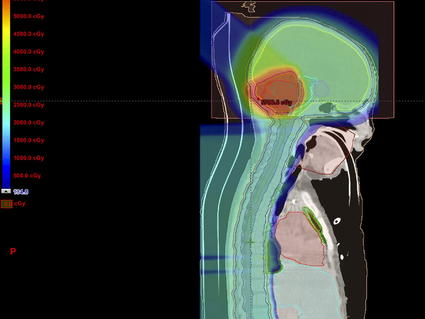

But any discussion of progress also requires that we recognize where advancement has lagged. For some types of childhood cancer, such as soft tissue and central nervous system cancers, long-term survival is still poor and treatment advances have been limited. Moreover, children cured of their cancer may face a lifetime of health problems caused by their disease and its treatment, including aggressive surgeries, radiation, and chemotherapy.

A problem in clinical oncology is knowing the best treatment to give a patient. There are many medicines to treat cancer, and they can be combined with surgery and radiation in various complex regimens. But given all these possible choices for therapy, it is often not clear what is the best treatment for a given patient.

For many children, that may mean going on treatment for a few months, and then having imaging scans done to see if the cancer is regressing. But it’s also a few months where the cancer might be getting worse, a few months of potential side effects, a few months of costs associated with treatment, and a few months of anxiety and distress for the child and their loved ones.

It would be far better to be able, at the time of diagnosis, to know which treatment approach is most likely to work. Determining the best treatment would rely not just on findings from previous trials but also specific information about the patient and their cancer. We don’t collect this molecular information uniformly today—and even when we do collect it, we don’t know how to interpret it completely to make these therapeutic decisions, particularly in children.